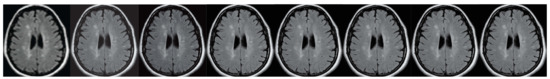

Figure 7. The brain imaging results. From left to right: A: Image reconstructed from partially sampled PROPELLER blade, B:Cartesian sampling grid without image registration applied (with no downsampling applied), C: B-spline Cubic interpolation, D: Non-Rigid Multi-Modal 3D Medical Image Registration Based on Foveated Modality Independent Neighbourhood Descriptor [45], E: Enhanced deep residual networks for single image super-resolution [14], F: Image super-resolution using very deep residual channel attention networks [16], G: Residual dense network for image super-resolution [15], H: super-resolution with proposed sampling scheme and motion compensation (the proposed algorithm). Compression ratio is 50%. Please see Table 2 for the PSNR values at other compression ratios.